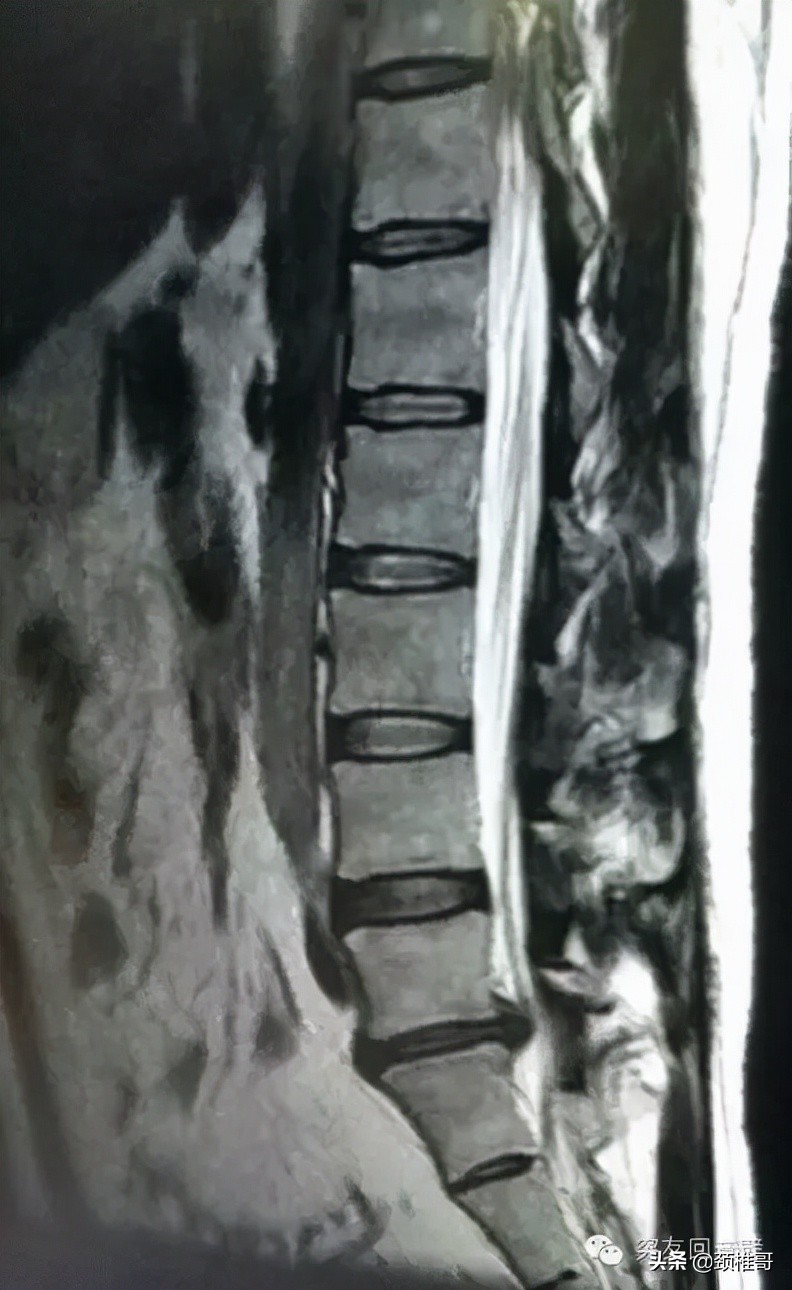

21日早晨臀部左侧也开始疼痛,走路跛行,左脚只能在地上拖着走。我去医院看病,医生说是腰突急性发作,经核磁检查被诊断为L5/S1椎间盘原位突出,L4/5椎间盘膨出。我便办理了住院手续,每天上午做理疗,中午开车回单位上班,有时间就躺会儿。十来天后腰部胀痛,左脚又酸又胀,而且有麻木感,总体来说略有缓解而已。因为事情太多,4月2日我办理了出院手续。

图2:2016年3月21日核磁影像资料